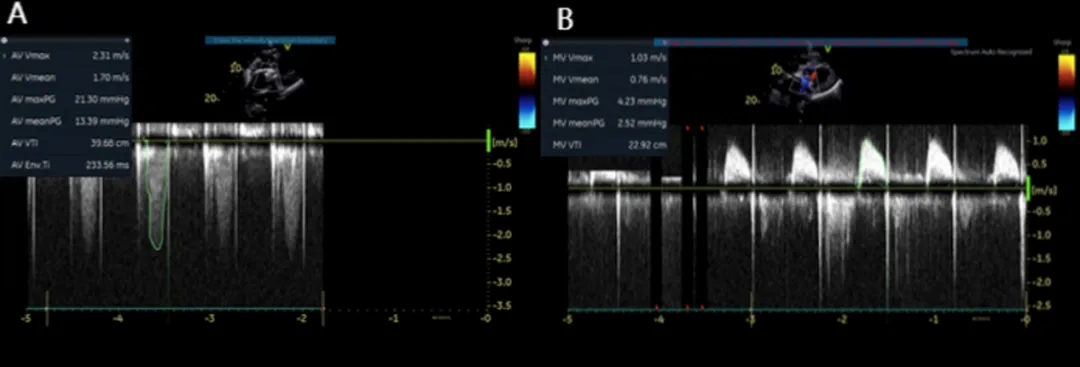

2025年6月4日,在全身麻醉下,通过TEE和荧光镜引导进行手术。通过右颈内静脉建立临时起搏。经左前外侧小切口暴露第五肋间隙,使用双重荷包缝合固定心尖;静脉注射肝素使活化凝血时间(ACT)>250秒。心尖穿刺后,先使用软导丝穿过主动脉瓣口,随后更换为Amplatz超硬导丝(波士顿科学公司)。在快速起搏(180次/分)下,使用18mm球囊对主动脉瓣生物假体进行预扩张。选择21mm ScienCrown瓣膜,旋转手柄将瓣膜从输送系统中逐步释放(视频1)。瓣膜成功植入后,无错位或瓣周漏(PVL)(图2B及视频2)。TEE显示主动脉瓣平均跨瓣压差为6mmHg,无瓣周漏(图2C及D)。随后,使用硬导丝穿过二尖瓣生物瓣进入左心房(视频3)。在快速起搏(180次/分)下于二尖瓣位置植入25mm ScienCrown瓣膜(图2E及视频4)。TEE显示二尖瓣平均跨瓣压差为5mmHg,瓣叶运动正常,无瓣周漏(图2F)。术后荧光检查显示两枚瓣膜均位置良好(图2G)。术后第一天床旁TTE显示二尖瓣压差2.52mmHg,流速0.76m/s;主动脉瓣压差13.39mmHg,流速1.7m/s,提示轻度主动脉瓣狭窄(AS)和正常二尖瓣功能(图3)。患者心功能改善至NYHA II级,并在术后第5天出院。

图3. 术后经胸超声心动图检查结果